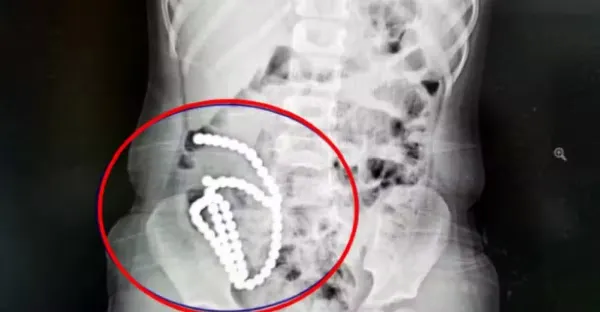

4歲女童照X光驚見「肚裡一串白珠珠」,真相揭曉竟是哥哥在玩!母親崩潰證實,醫生無奈嘆息:恐怕一輩子都毀了